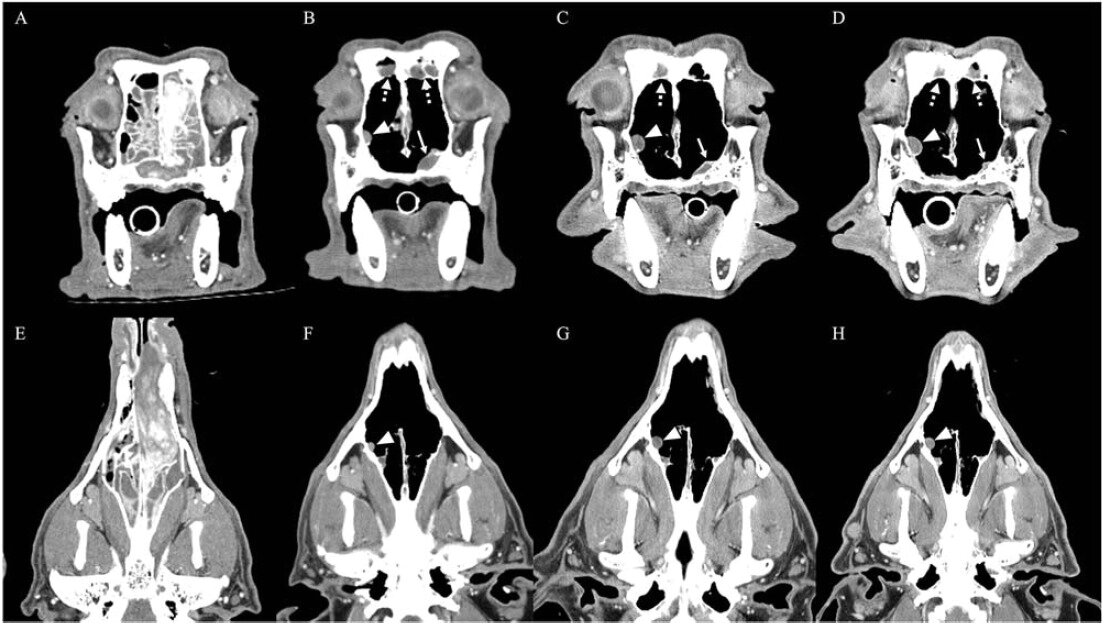

본문 이미지 - 비강 종양이 발생한 반려견의 컴퓨터 단층촬영 영상(본동물의료센터 제공) ⓒ 뉴스1

비강 종양이 발생한 반려견의 컴퓨터 단층촬영 영상(본동물의료센터 제공) ⓒ 뉴스1